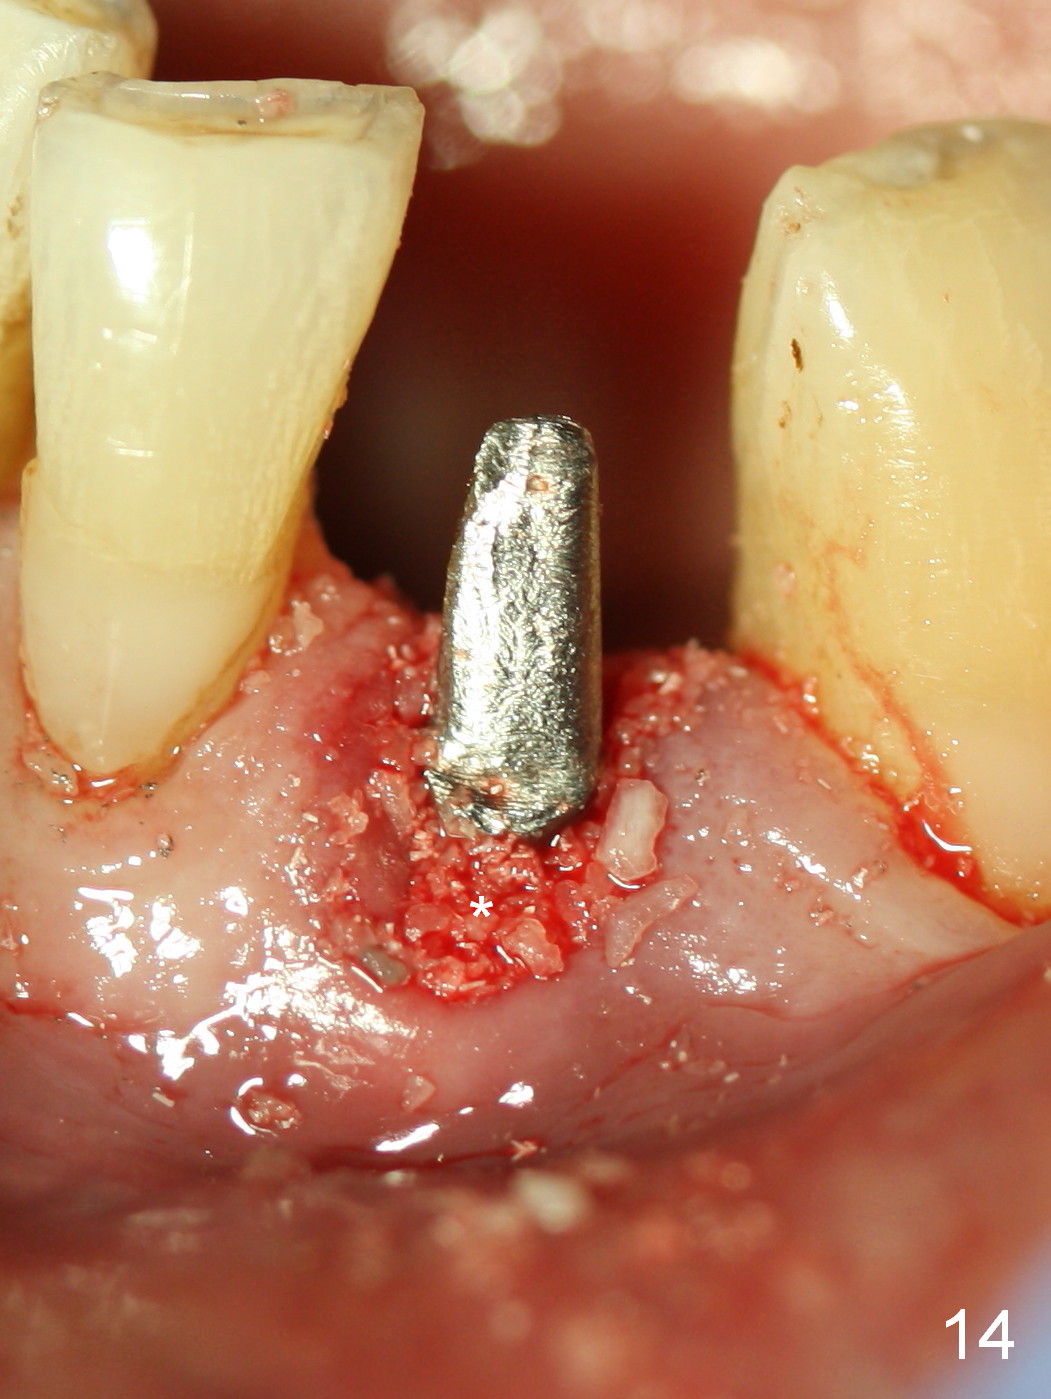

A 74-year-old man has several missing teeth (Fig.1). His 1st goal is to replace the lower left lateral incisor (Fig.2). The residual root has an apical lesion (Fig.3 *). To describe intraop findings, a CT image of a different patient is used (Fig.4 coronal section; B: buccal; L: lingual). After extraction, the buccal plate is found to be thin and low (Fig.5 arrowheads). A 1.5 mm pilot drill (Fig.6 red line) is used to initiate osteotomy in the lingual plate of the socket. Once the drill penetrates the lingual plate, the trajectory changes and the depth is 17 mm from the gingival margin (Fig.7). A PA is taken (Fig.8); it appears that the osteotomy can be extended more apically. When the pilot drill extends to 20 mm, there is sudden empty feeling. The lingual plate has perforated (Fig.9). A new osteotomy is established buccally (Fig.10 pink). To avoid buccal plate perforation, especially in the buccal undercut area (>), the coronal end of the drill has to be tilted buccally (<--). An angled abutment (3x20 mm, 15°) is placed (Fig.11,12). The abutment is modified (Fig.13,14) to accommodate an immediate provisional (Fig.15,16 P). Perio dressing is to be applied to prevent the bone graft from getting dislodged buccally (Fig.15). The dressing is in place 7 days postop (Fig.17).